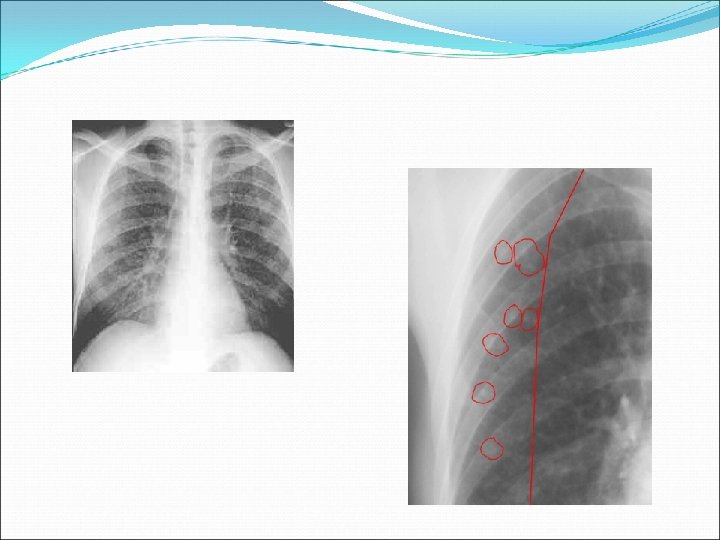

Endothoracic Pulmonary 1 ary pulmonary complex Adenopathy large w/ small parenchymal foci CXR hilar adenopathy, localized hyperaeration, atelectasis localized pleural effusion segmental infiltrate (foci) Signs/symptoms infrequent (except in infants) 1 ary complex: fever + cough Fever, cough, night sweats, FTT Localized wheeze, diminished BS Dysphagia, edema hand/arm

Hilar Adenopathy